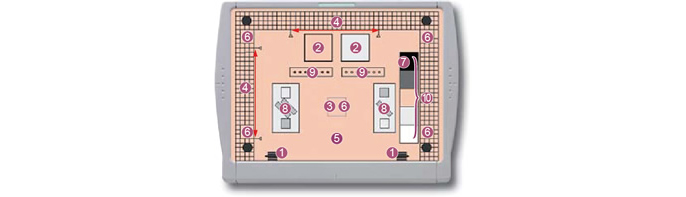

O programa consiste no exclusivo “FCR 1 Shot Phantom M Plus” e no “Software/Guia FCR Mammography QC”.

Configuração do 1 Shot Phantom no equipamento de mamografia

Dimensões: 263 mm(l) x 198 mm(p) x 24 mm(a)

Peso: 575 g

| Teste de instalação |

|

|---|---|

| Teste diário/semanal |

|

| Teste trimestral | Repetir análise |

| Teste semianual |

|

| Teste anual |

|

| Aplicável por: |

|